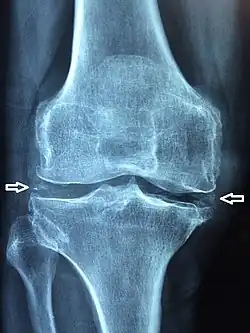

La chondrocalcinose articulaire (CCA), maintenant renommée rhumatisme à pyrophosphate de calcium (PPC)[1],[2],[3] est une arthropathie microcristalline caractérisée par la précipitation de cristaux de pyrophosphate de calcium dihydraté (en) dans les tissus articulaires et périarticulaires. Elle entraîne une calcification intra-articulaire sous la forme d'un liseré opaque fin, cernant les contours articulaires à quelques millimètres de l'os sous-chondral.

La chondrocalcinose est asymptomatique dans 25 % des cas. La découverte est radiologique. Les articulations les plus touchées sont les genoux, les poignets, et le bassin.

La forme pseudo-arthrosique représente 50 % des cas. Plus sévère que l’arthrose classique, la clinique est marquée par des arthralgies chroniques de types mécaniques et les radiographies montrent des signes classiques d’arthrose associés à des liserés typiques de la chondrocalcinose dans le cartilage et dans le fibrocartilage (les ménisques par exemple). Les articulations les plus souvent touchées sont la scapho-trapézienne, le poignet, les chevilles et les métacarpo-phalangiennes[6].